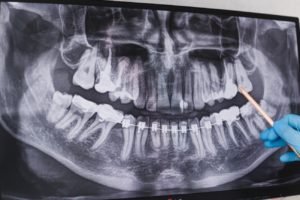

Las revisiones dentales regulares son fundamentales para el mantenimiento de los implantes dentales. Tu dentista puede evaluar la salud de tus implantes, encías y dientes naturales, identificar problemas potenciales y realizar limpiezas profesionales. Se recomienda una visita al menos cada seis meses, o según las indicaciones de tu dentista.